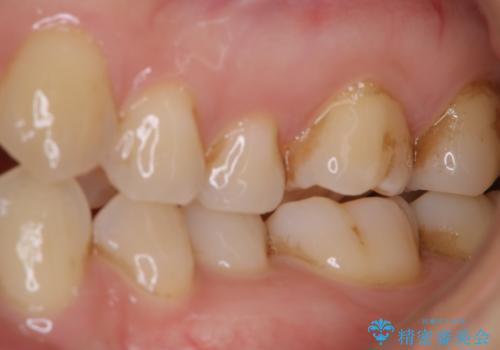

歯磨きをしても奥歯のザラつきが取れない

- 毎日歯磨きをしているのに、奥歯のザラつきが気になるとのことでした。プラーク・歯石・ステインが付着していたためPMTC60分コースを行いました。